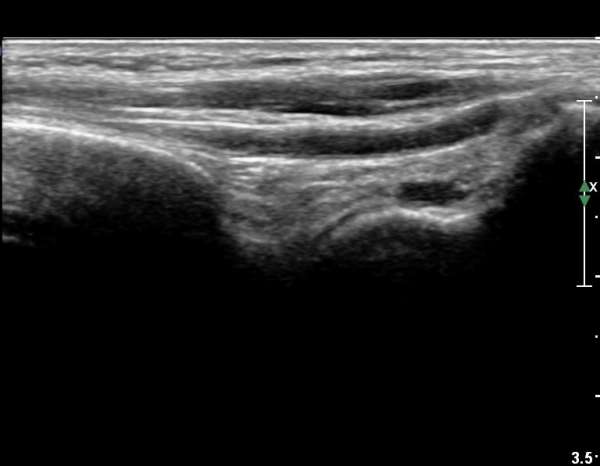

Àü°ÅºñÀÎ´ë ºÎÇϰ˻翡¼­ ÀδëÆÄ¿­ ºÎÀ§°¡ ¹ú¾îÁö°í °Å°ñÀÌ ¾ÕÀ¸·Î ´Ü°ÜÁö´Â ¼Ò°ßÀ» º¸ÀÓ(»çÁø 3, 4, ÷ºÎ µ¿¿µ»ó).